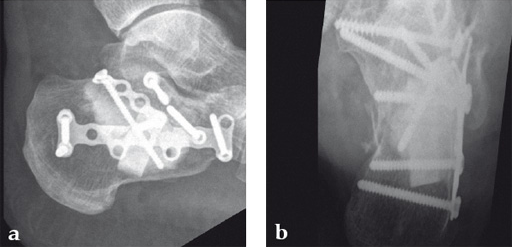

Case 1: A 70-year-old man sustained a Sanders IIA fracture of his left calcaneus.

(Case provided by Michiel Verhofstad, Tilburg, The Netherlands)

After open reduction a gap was left due to impaction of the osteoporotic metaphyseal bone. To support preliminary maintenance of the primary reduction a block of calcium phosphate was introduced beneath the posterior facet. The rest of the gap was filled with Norian drillable. After hardening plate osteosynthesis was performed. Two screws were placed through the fiber-enhanced calcium phosphate. Weight bearing was started 6 weeks later. After 6 months the fracture was healed without secondary loss of reduction. Note that at that time the degradation of the void filler is visible.